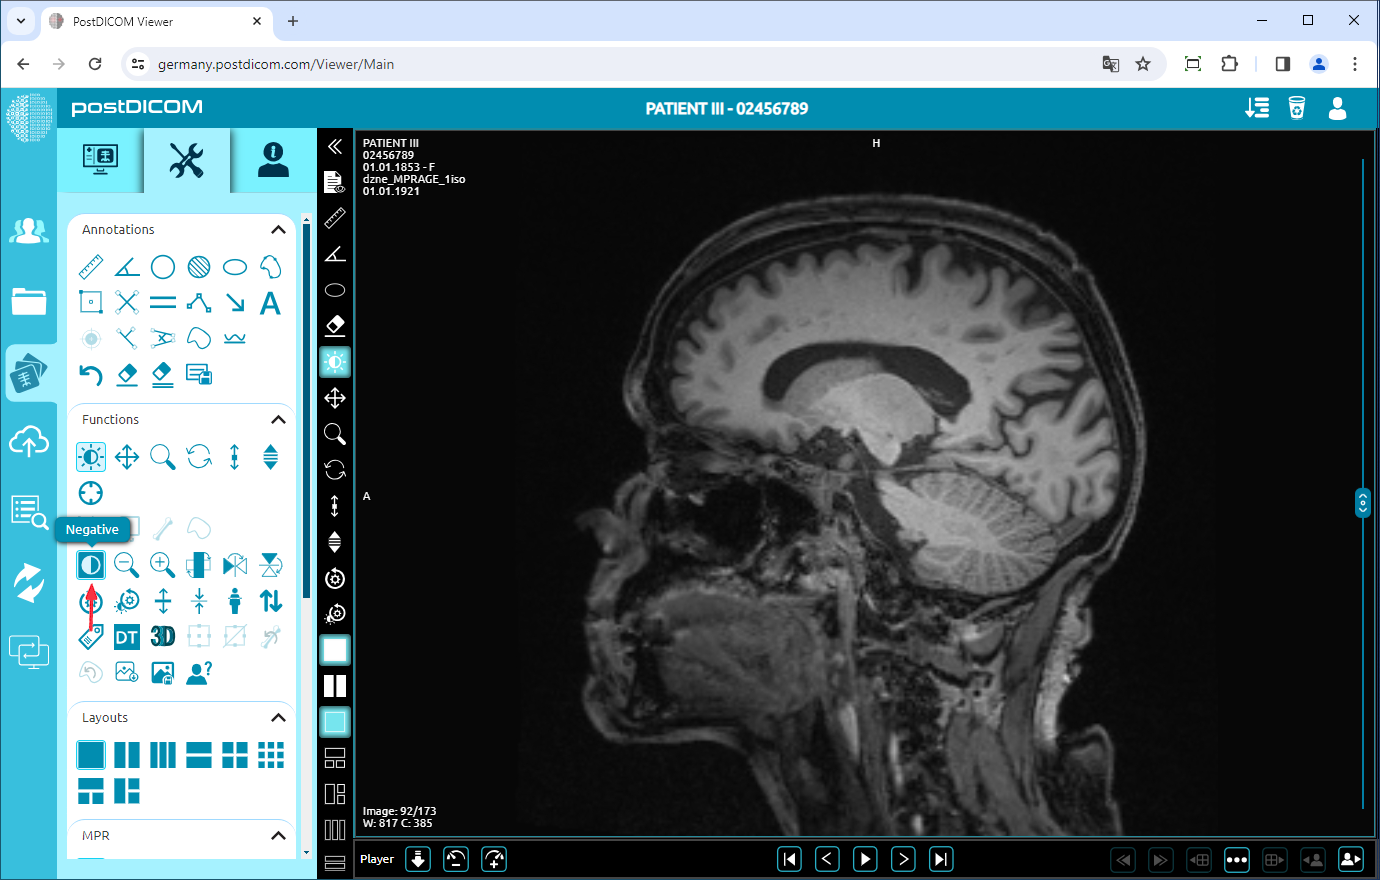

Negate

To negate the image, click on the “Negative” icon on the left side of the page.

After clicking, you will see the inverted image on the viewport. If you want to see normal image click again.